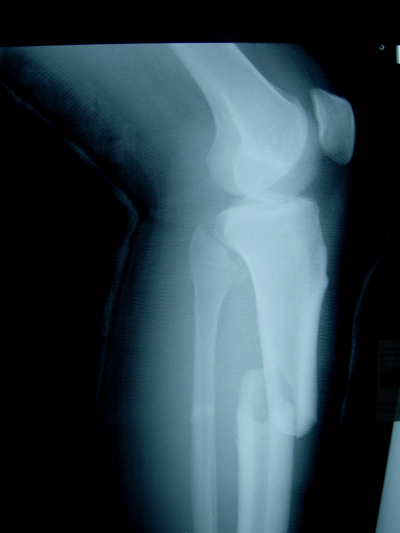

骨折圖片